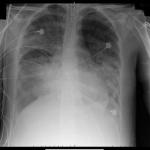

One of the earliest (of many) bizarre symptoms of COVID-19 was blood clotting in the lungs. These clots could easily be seen when an endotracheal tube was removed from a ventilated patient.